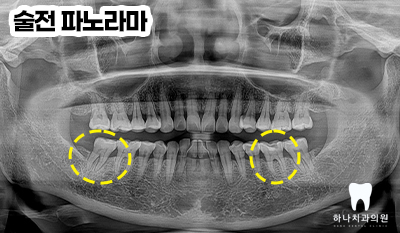

위 환.자분은 50대 여성분으로

오른쪽 아래 가장 안쪽 어금니가

밥을 먹을 때마다 깜짝 놀랄 정도로

통증이 느껴지신다고 하셨고

왼쪽 아래 치아는 깨졌다고

말씀해 주셨습니다.

양쪽 아래 어금니가 파절된 이유로

내원해 주셔서 두 치아의 진.단은

파절에 해당하지만 그 양상과

치료 방법이 달랐는데요.

오른쪽 아래 어금니의 경우

사진에서 명확하게 보이지는 않지만

뿌리 끝까지 진행된 치아의 수직 파절로

탐침자로 만져보았을 때 완전히 반으로

갈라져 있는 상태였습니다.

왼쪽 아래 어금니는 다행히도

치아머리 부분만의 파절을 관찰하여

오른쪽은 발치 후 임플란트 수복,

왼쪽은 신경치료 후 크라운 수복을

계획하였습니다.